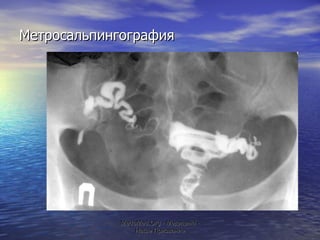

Метросальпингография MeduMed.Org -  Медицина - Наше Призвание